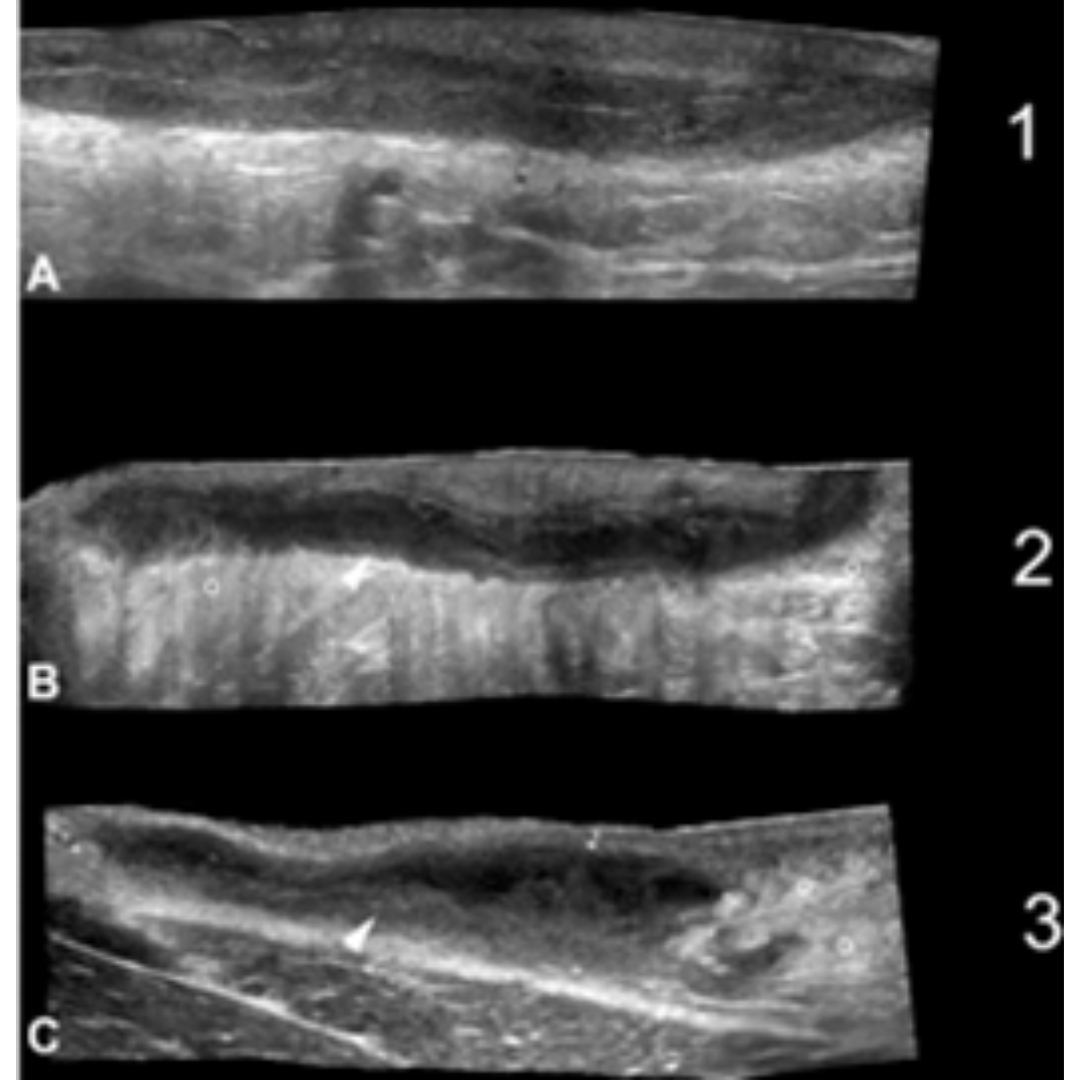

Figura 7: A a D de menor a mayor edema. Se muestra la clasificación de Edema hipodérmico (o) adyacente los trayectos de folículos de HS. Se observan imágenes en modo B con campo de visión extendido demostrando el eje largo de las fistulas (*). En D una vista transversal del trayecto fistulosos (*) es mostrado con grado 2 de edema (o). Se observa liquido hipoecoico (puntas de flechas negras) entre los lóbulos grasos en D*.

Figura 8: El signo de halo (flechas) en HS representa trayectos fistulosos con cicatrización fibrótica grado 2. B, C y D muestran diferentes tractos fistulosos con cicatrización fibrosa grado 2. Note el borde hipoecogénico (puntas de flechas oblicuas) rodeando las fístulas. Los fragmentos lineales hiperecogénicos en algunas de las fistulas sugieren fragmento del tracto piloso (flechas verticales en A y C)

Figura 9: Tipos de fístulas de tractos en HS. Clasificación tipo 3 (C) muestra el borde grueso hipoecogénico (punta de flecha), que sugiere cicatrización fibrótica en la periferia del trato fistuloso y el edema (o) del tejido graso hipodérmico en comparación con los tipos anteriores. (o) edema hipodérmico; es un marcador positivo de los bordes del trayecto fistuloso.